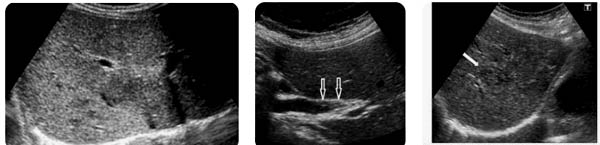

-Hình ảnh tổn thương gan ở bệnh nhân tái khám sau điều trị thuốc đặc hiệu triclabendazole (biệt dược Egaten® hoặc Lesaxys®hoặc Deworm®):

+Sự hồi phục của gan sau 1-3-6 tháng điều trị bằng triclabendazole khác nhau ở trên các bệnh nhân, có lẽ phụ thuộc kích thước ổ tổn thương, thời gian mắc bệnh trước khi được điều trị và sức đề kháng của bệnh nhân;

+Một số ít trường hợp mất hẳn khối tổn thương chỉ sau 1-2 tháng điều trị dù trước đó có khối thương tổn khá lớn;

+Một số trường hợp còn quan sát được một khối nhỏ có độ hồi âm ít rõ sau nhiều tháng kể từ khi dùng thuốc đặc hiệu triclabendazole;

+Thường sau 2-3 tháng điều trị, còn khoảng 50% trường hợp thấy kích thước khối tổn thương không thay đổi, nhưng tính chất hồi âm có thay đổi rõ rệt, với nhiều vùng chuyển từ giảm âm hoặc hỗn hợp âm sang tăng hồi âm bên trong (quá trình tăng xơ hoá làm lành vết thương) làm cho khối tổn thương nổi bật lên dễ quan sát, các khối trống âm (microabces có dịch nên trong) có thể nhỏ lại hoặc biến mất.

Tuy nhiên, có một số ít trường hợp, sau 3 tháng điều trị bằng triclabendazole (TCBZ) hình ảnh khối tổn thương gan do SLGL không thay đổi đáng kể về kích thước cũng như tính chất hồi âm. Trong những trường hợp này chúng tôi cũng chưa xem đó là điều trị thất bại nếu tình trạng lâm sàng có cải thiện tốt, bệnh nhân được theo tiếp vào tháng thứ 6 sau điều trị.

-Hình ảnh tổn thương gan ở bệnh nhân tái khám sau 6-9 tháng điều trị:

+Trên 70% trường hợp siêu âm ở bệnh nhân sau 6-9 tháng điều trị thấy độ hồi âm của gan trở lại bình thường nhưng có thể nhìn thấy sẹo;

+Số còn lại thường có các kiểu hình ảnh sau: độ hồi âm của gan thô, không đồng dạng; hoặc một vùng gan có độ hồi âm tăng nhẹ so với vùng nhu mô lành xung quanh; hoặc một khối tăng âm, giới hạn rõ so với tổ chức xung quanh, trong trường hợp khối có kích thước nhỏ khó phân biệt với hình ảnh u mạch (hemangioma);

+Một tỷ lệ rất thấp (< 5% trường hợp) có hình ảnh khối tổn thương không thay đổi về cả kích thước lẫn tính chất hồi âm, hình ảnh quan sát được vẫn là một khối có độ hồi âm hỗn hợp, trên nền khối giảm âm có nhiều đám tăng âm và trống âm xen kẽ. Các trường hợp này có thể được xem là điều trị chậm lành và có thể “thất bại điều trị” và nên dùng lại liều thứ 2 của triclabendazole liều gấp đôi (20 mg/kg cân nặng).

-Hình ảnh tổn thương gan ở bệnh nhân tái khám sau 12 tháng điều trị: Nhìn chung, hầu hết trường hợp tái khám sau 12 tháng hình ảnh siêu âm gan trở lại bình thường. Một số ít trường hợp quan sát được khối tăng âm nhẹ, kích thước nhỏ.